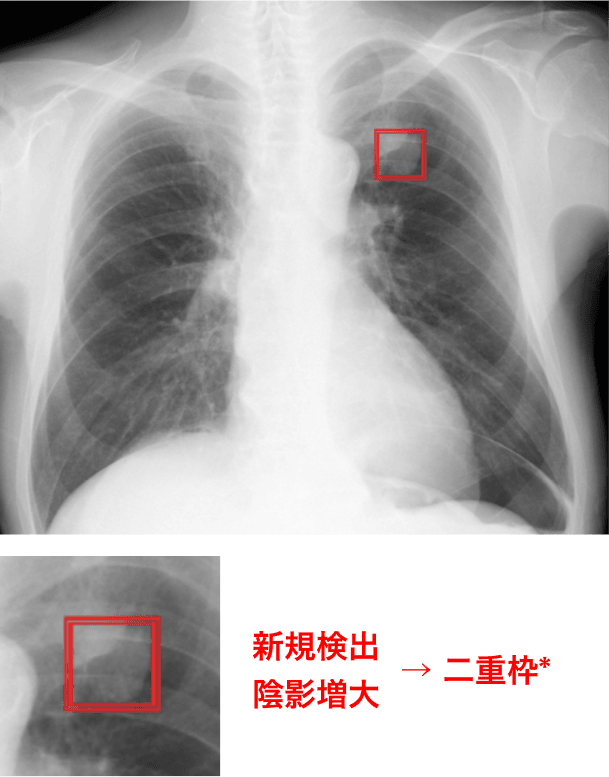

過去画像との比較をサポート

過去に解析された同一患者の胸部X線画像と現在の画像を自動で比較し、異常陰影候補領域の経時的変化を表示します**。

過去比較

過去に撮影された同一被験者の胸部X線画像を比較し、異常陰影候補領域の経時的変化を強調表示します。

<例>

* Noduleモードの場合。XRモードの場合は、新規検出のみ